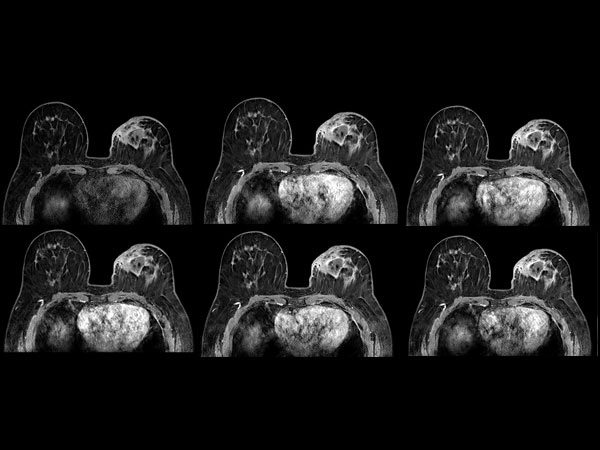

Dynamic axial eTHRIVE

-